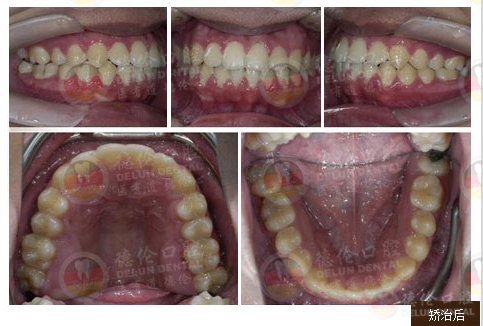

小俊 11岁(替牙期)

牙齿症状:龅牙

治疗方法:自锁托槽矫正

术后效果:解决嘴唇突出的问题,面部美观也得到协调